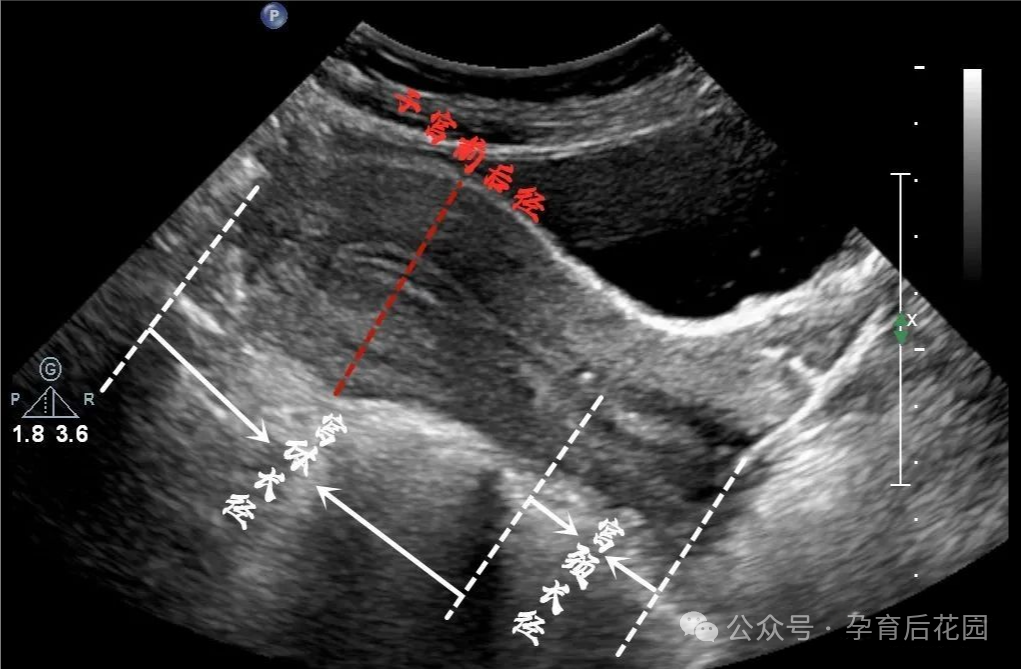

医生一般通过 B 超测量子宫大小,但这里面有不少门道。比如测量长度时,只算子宫体(从宫颈内口到子宫顶),不算宫颈;测厚度和宽度,要找子宫最 “胖” 的位置。而且,如果子宫是弯曲的(前屈或后屈),还得分段测量再相加,不然数据就不准了!

曾经有位大学生,子宫前后径仅 1.8cm,四处求医被告知 “无法生育”,整个人都快抑郁了。后来我们建议她先观察,配合适当治疗,一年后复查,子宫大小完全恢复正常。所以说,年龄、个体差异、检查方法都会影响判断,千万不要自己吓自己!